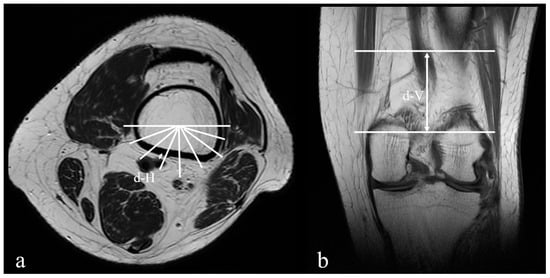

| d-H (mm) | 7.92 ± 3.42 | 6.76 ± 2.86 | 0.010 |

| d-V (mm) | 61.79 ± 9.39 | 51.54 ± 10.49 | <0.001 |